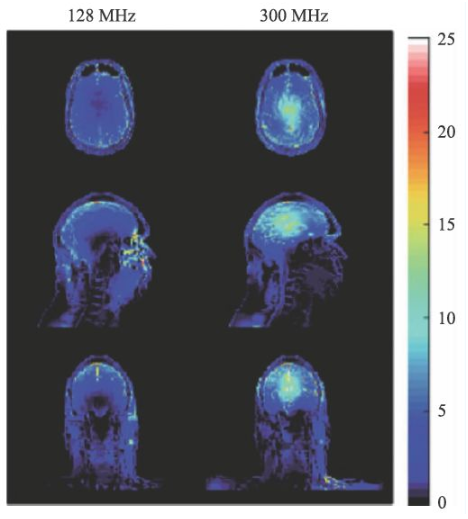

SAR值升高是射頻場另一個問題,隨著射頻頻率的提高,組織對射頻能量的吸收急劇上升,可導致組織局部的溫度升高。SAR值的計算可由式9表示。

σ為組織電導率,ρ為組織密度。對于SAR值各國和國際組織均有嚴格的限制,因為過量的射頻能量的吸收可能會對受試者造成危害。

圖14 是一個SAR值對大腦溫度升高的一個仿真結果[14],對于平均SAR=3 W/kg的頭部掃描,7 T(右側)下的溫度升高顯著高于3 T(左側)。因此在超高MRI中均需要配置一個可靠的SAR值監控裝置。

圖14 局部SAR值的仿真結果